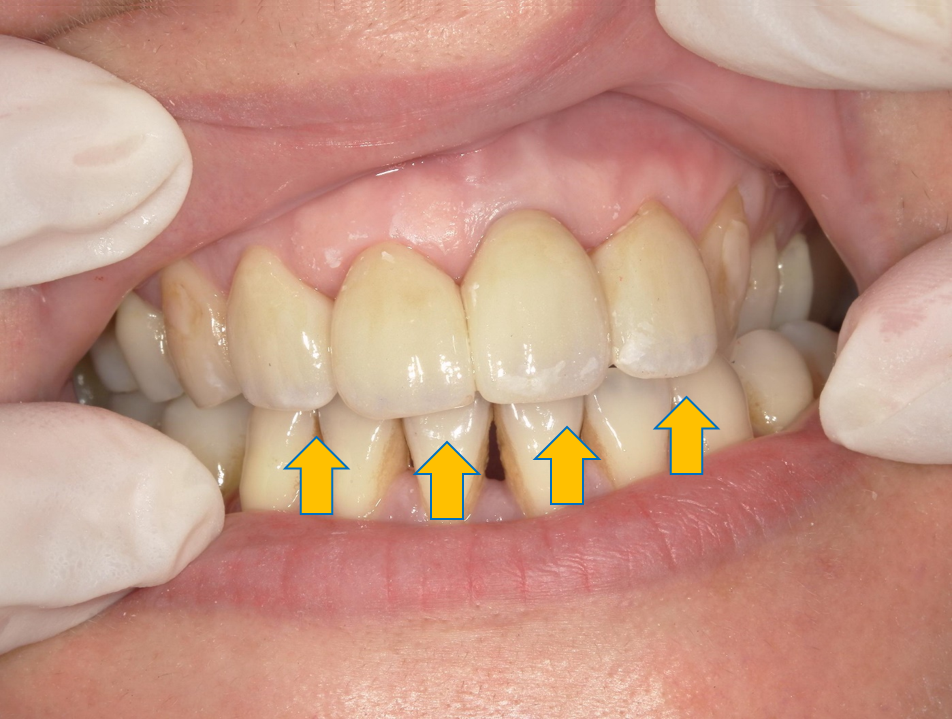

案例 3 術前(Before)

蛀牙及變色,影響咀嚼與美觀不佳

案例 3 術後(After)

門牙重建,恢復咀嚼功能與外型美觀